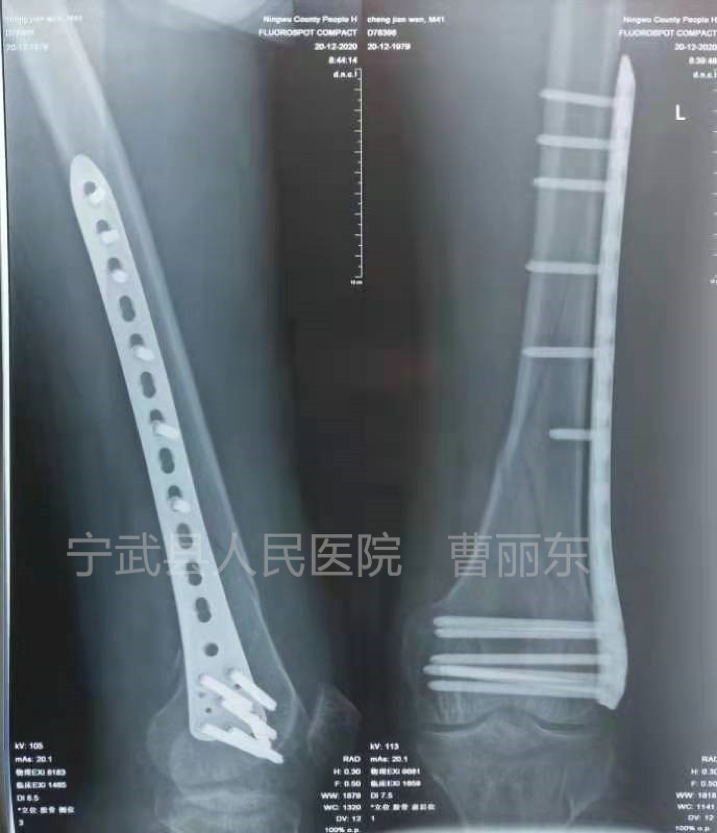

一例股骨髁骨折

微创钢丝捆扎复位

复位后安放钢板,拧入螺钉固定

术后拍片骨折复位良好,内固定钢板位置良好。